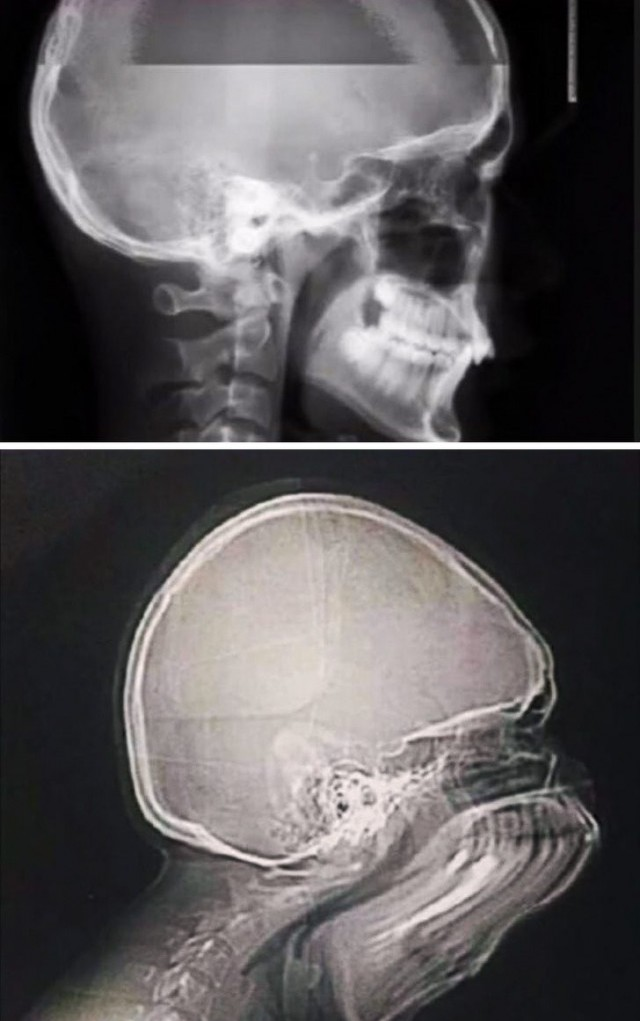

Что будет если чихнуть во время рентгена головы?